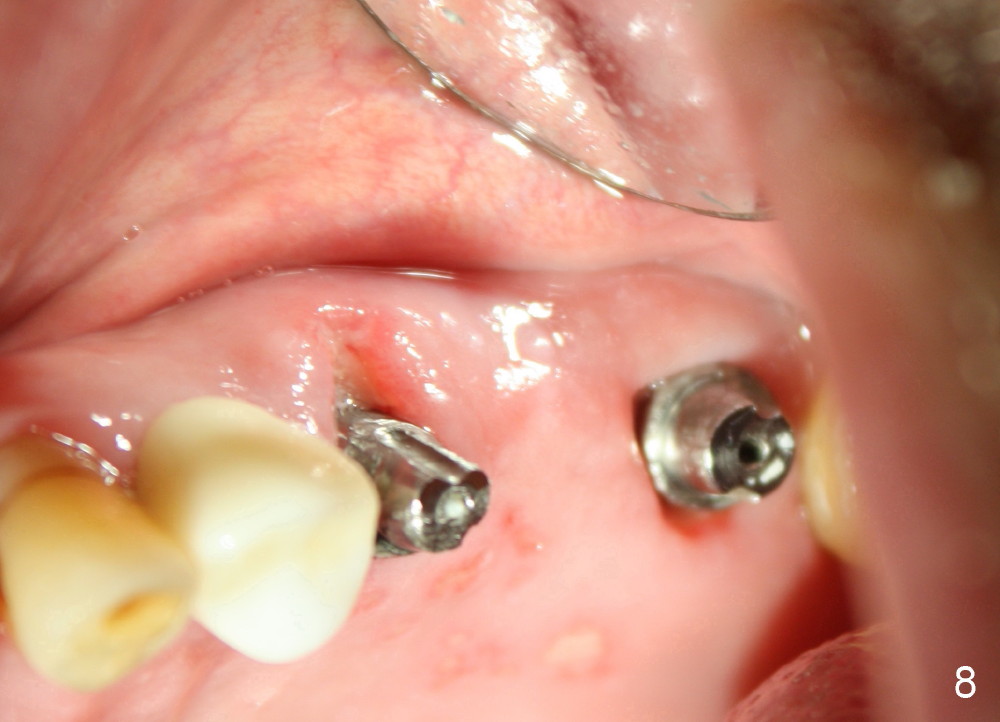

A 84-year-old man has a failing bridge.  A short implant was placed at the pontic site 5 months ago (Fig.1, taken 2 months postop).  The bridge was temporarily recemented.  It is planned at next appointment to extract #13, uncover the implant at pontic and save #15 if possible.  When the bridge is removed, the tooth #15 is also found non salvageable (Fig.2). The root stump of #15 is oval, 5x10 mm.  Preop PA shows that the 2nd molar has two roots (Fig.1: *).  When the tooth is extracted, the septum is found wide buccolingually (Fig.3: S, between the buccal (B) and palatal (P) sockets).  Osteotomy is formed in the septum with combination of drills and osteotomes, followed by insertion of taps (Fig.4).  Finally the osteotomy (Fig.5 O) in the septum (S) of #15 deviates into the buccal (B) socket.  When the implant is placed (Fig.6), it deviates buccally slightly (Fig.7).  The remaining sockets are filled by bone graft (Fig.7 G).  Immediate provisional bridge is fabricated after placement of abutments (A).  The main purpose of the provisional at early stage is to hold bone graft in place.  There is no occlusal contact with the opposing dentition,  Due to time constraint, the uncovering of #14 is postponed.  The provisional dislodges 2-3 days postop.  The patient returns for recementation 5 days postop; the sockets have initially healed (Fig.8,9, as compared to Fig.7).

The provisional dislodges once more several days later.  The implant at the site of #14 is uncovered; an abutment (A) is placed (Fig.10.11); a provisional (Fig.12 P) 3-unit bridge is fabricated and cemented securely.  There is some occlusal contact with the opposing teeth.